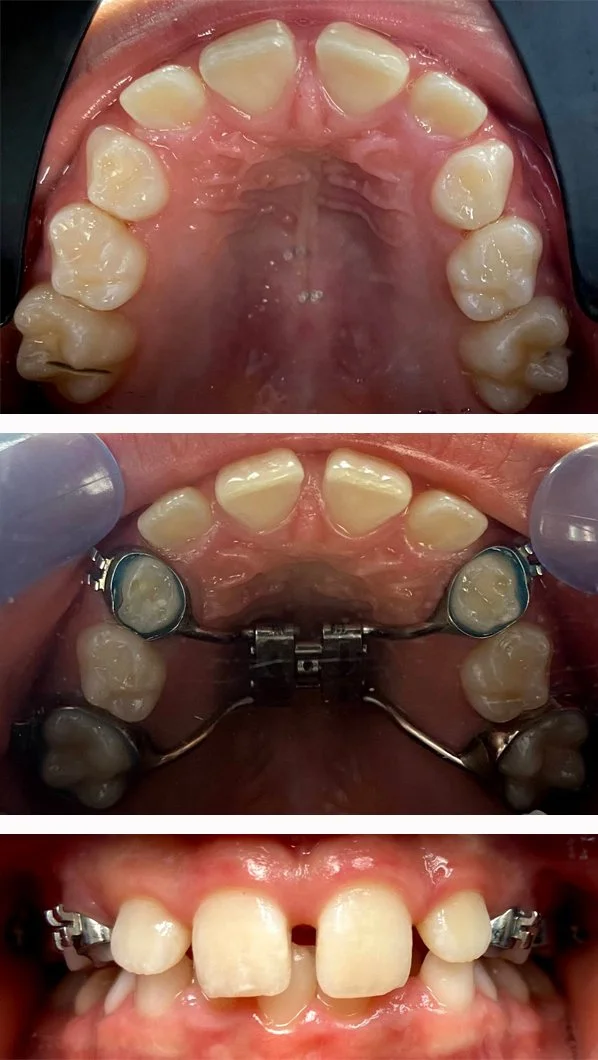

Orthodontics

Movement of teeth to improve function and appearance with Invisalign

Invisalign

Before and after appliance

Orthodontic Appliance